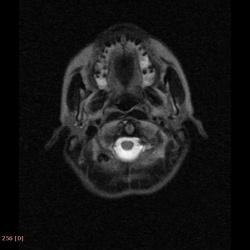

Мужчина 30 лет, в/в наркоман, ВИЧ инфекция.